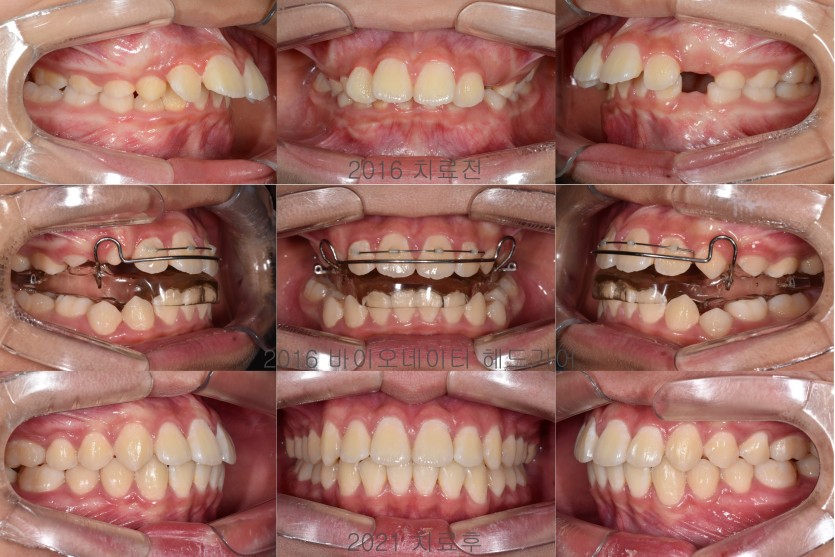

무턱의 성장조절 치료 151회

무턱을 지닌 청소년 환자들의 경우에는 안면 골격의 성장조절 치료를 진행할 수 있습니다.

사춘기는 성장이 급속하게 일어나는 시기이므로 상악의 성장을 헤드기어라는 장치를 통해 제한하고

바이오네이터라는 장치로 하악의 성장을 유도합니다.

2년 정도의 장기간 치료가 필요하며 그 기간동안 성실하게 장치를 착용해주어야 합니다.

헤드기어의 치료는 예측 가능하며 협조가 충분할 경우 상악의 성장 제한을 기대할 수 있으나

바이오네이터는 치료 반응이 좋을 수 있는 안모인지를 분류해야하며

하악의 성장이 적극적으로 일어난다기보다는 치조골의 변화를 통해 안면 골격의 편차를 극복하는 방법입니다.